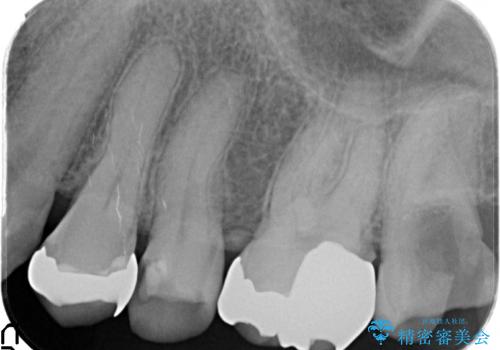

- 左上5番目の歯の銀歯が外れてしまったため、セラミックインレーによる修復を行った症例です。

手前の左上4番目の歯も虫歯だったため、セラミックインレーによる修復を行いました。

虫歯治療は虫歯の進行度によって処置が変わってきます。

虫歯が小さければ、インレー・クラウン等による修復・補綴処置を行うだけで済みます。

しかし虫歯が大きくなると神経処置や抜歯等をしなければならない場合もあります。